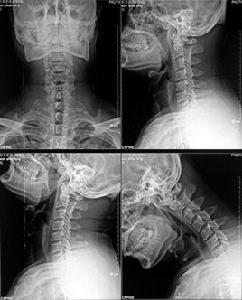

CT檢查技術,經過多次升級換代,其結構和性能不斷完善和提高,由最初的頭顱普通CT發展到螺鏇CT和電子束CT。CT檢查常規採用橫斷層面掃描,常用檢查技術有CT平掃、增強掃描、造影CT檢查等,掃描方法的選擇取決於檢查部位和檢查目的。顱腦、頭面、頸部、胸部、腹部、盆腔、脊柱和脊柱關節等雖然都可用CT檢查,但是從臨床套用效果上看也有一定的限制,如CT現實胃腸道腔內病變不如胃腸道鋇劑檢查顯示的清楚。